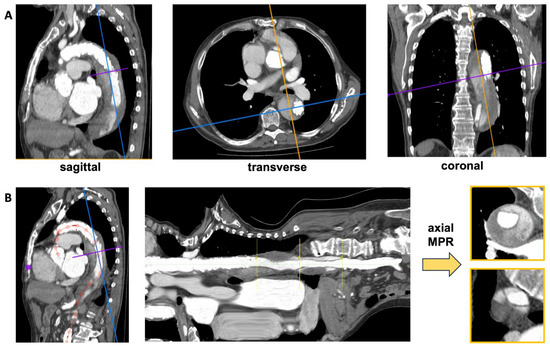

2.2. Image Pre-Processing